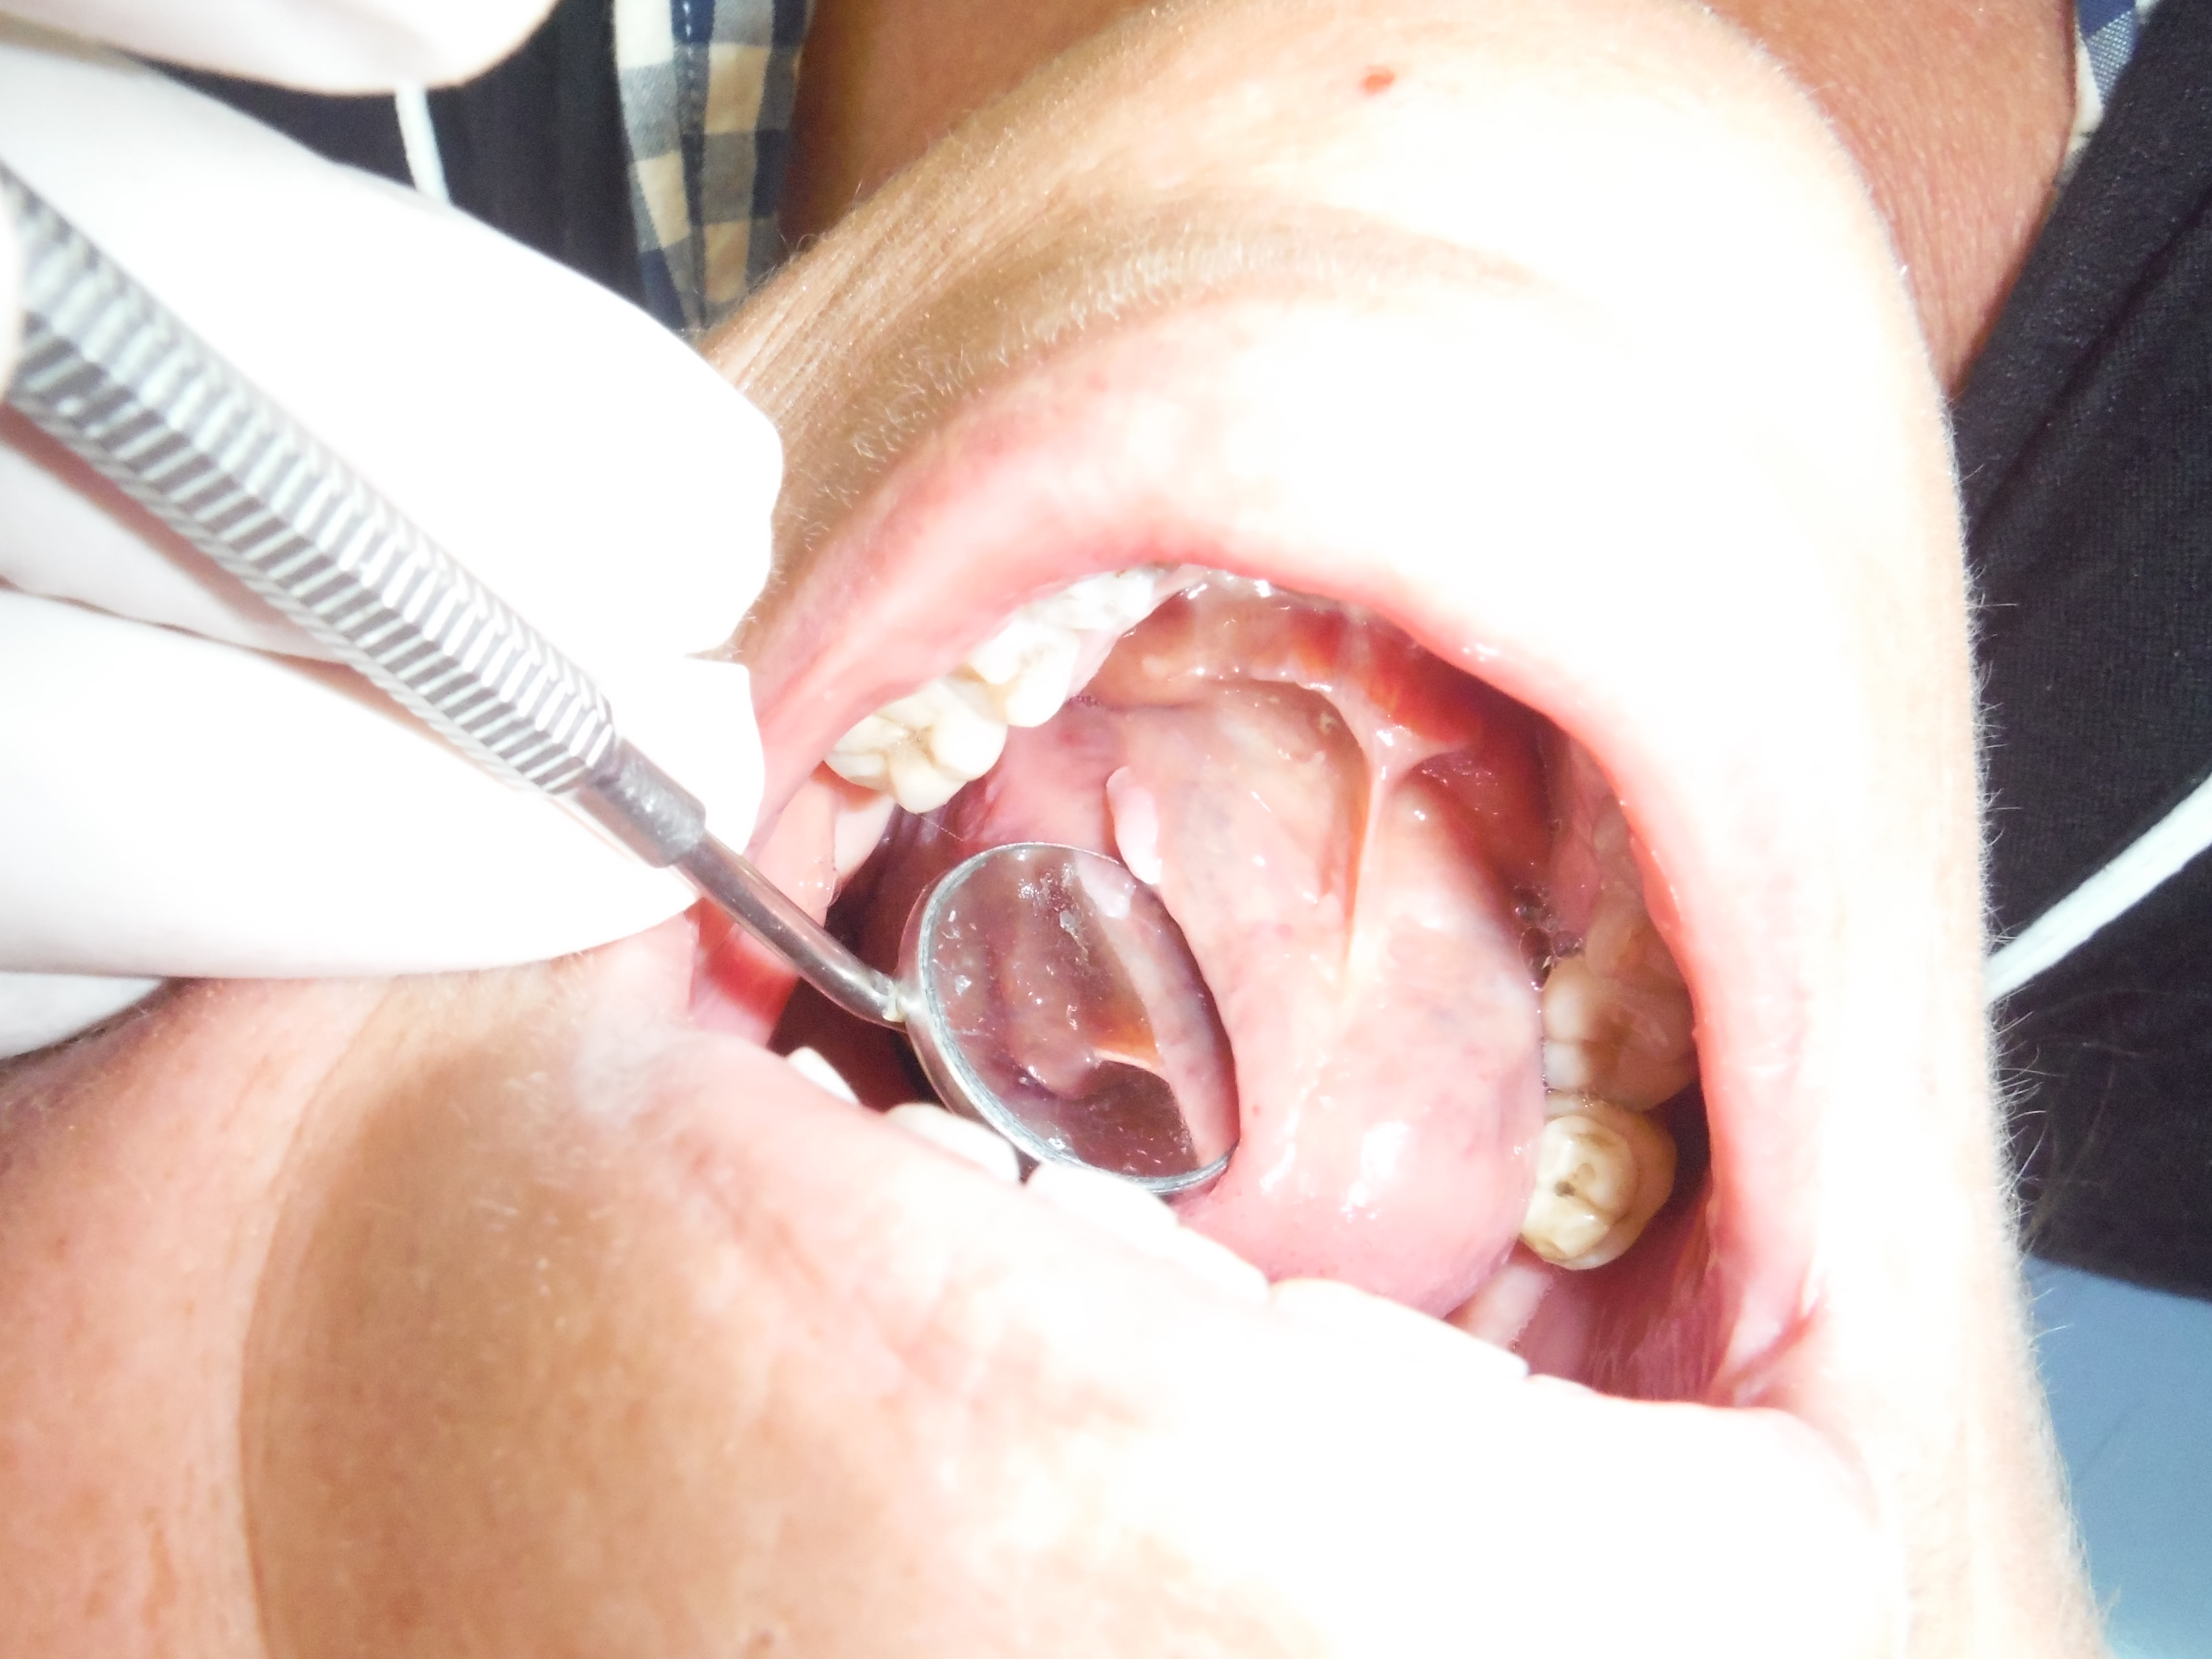

Patiente tabagique, un peu alcoolo, vient pour "j'ai l'impression d'avoir un cancer des gencives", forcement un problème paro+tabac c'est pas jojo, j'examine et puis il semble avoir aperçu un truc blanc, furtivement... "levez la langue..." Bingo! En vrai plus blanc que sur les photos et SURTOUT indétectable si on ne regarde pas sous la langue. Bon... exérèse et anapath, je fais pas, j'adresse, pas de chir pas de DASRI;-)))

Y a une induration ???

Non pas d'induration, c'est blanc de blanc , bien différencié, pas de saignement, la patiente n'avait pas remarqué, indolore. Je n'ai pas recherché de ganglion, j'aime pas trop tripoter les patientes, après elles s'attachent et t'as des soucis. Mon protocole est simple, j'ai un correspondant sto et il gère.